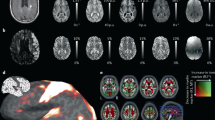

Data from all 12 healthy volunteers, including data from repeated scanning in 6 healthy volunteers, were processed successfully without having to discard any because of motion-related artifacts. Figure 3 shows example maps of the standard DTI metrics (AD/RD/MD/FA), DKI metrics (AK/RK/MK), qMT (BPF/T2B) and IR (qT1) in a single healthy control. Table 1 shows the mean (± SD) values of all qMRI metrics calculated in all study participants (N = 12), with the corresponding boxplots of all metrics shown in Fig. 4.

Example maps of standard diffusion tensor (DTI) derived metrics axial/radial/mean diffusivity (AD/RD/MD) and fractional anisotropy (FA), diffusion kurtosis imaging (DKI) metrics axial/radial/mean kurtosis (AK/RK/MK), quantitative magnetisation transfer (qMT) metrics bound pool fraction and bound pool transverse relaxation time (BPF/T2B) and quantitative longitudinal relaxation time (qT1), in the sciatic nerve of a healthy control.

Boxplots with mean (± SD) values of the standard diffusion tensor (DTI) metrics axial/radial/mean diffusivity (AD/RD/MD) and fractional anisotropy (FA), diffusion kurtosis imaging (DKI) metrics axial/radial/mean kurtosis (AK/RK/MK), quantitative magnetisation transfer (qMT) metrics bound pool fraction and bound pool transverse relaxation time (BPF/T2B) and quantitative longitudinal relaxation time (qT1), in the sciatic nerve of 12 healthy volunteers.